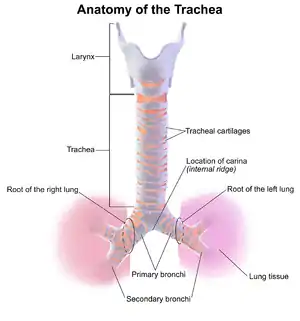

| Anatomy of the trachea | |